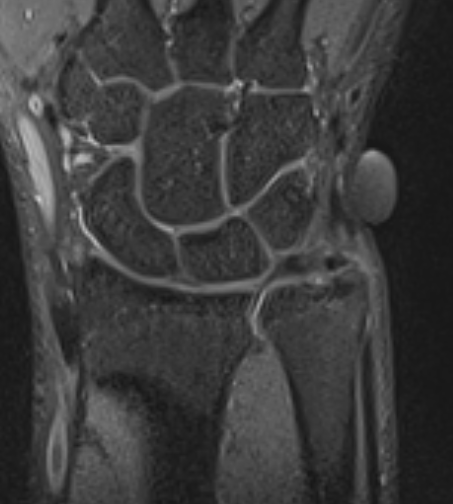

MRI

Kim et al Arch Orthop Trauma Surg 2023

- MRI of 54 patients with distal radius fracture and ulna styloid fracture

- tip ulna styloid fractures: 88% tears TFCC, 41% DRUJ instability after distal radius ORIF

- base ulna styloid fractures: 89% tears TFCC, 57% DRUJ instability after distal radius ORIF

Ulna styloid fracture with TFCC attached to fragment on MRI with partial tearing